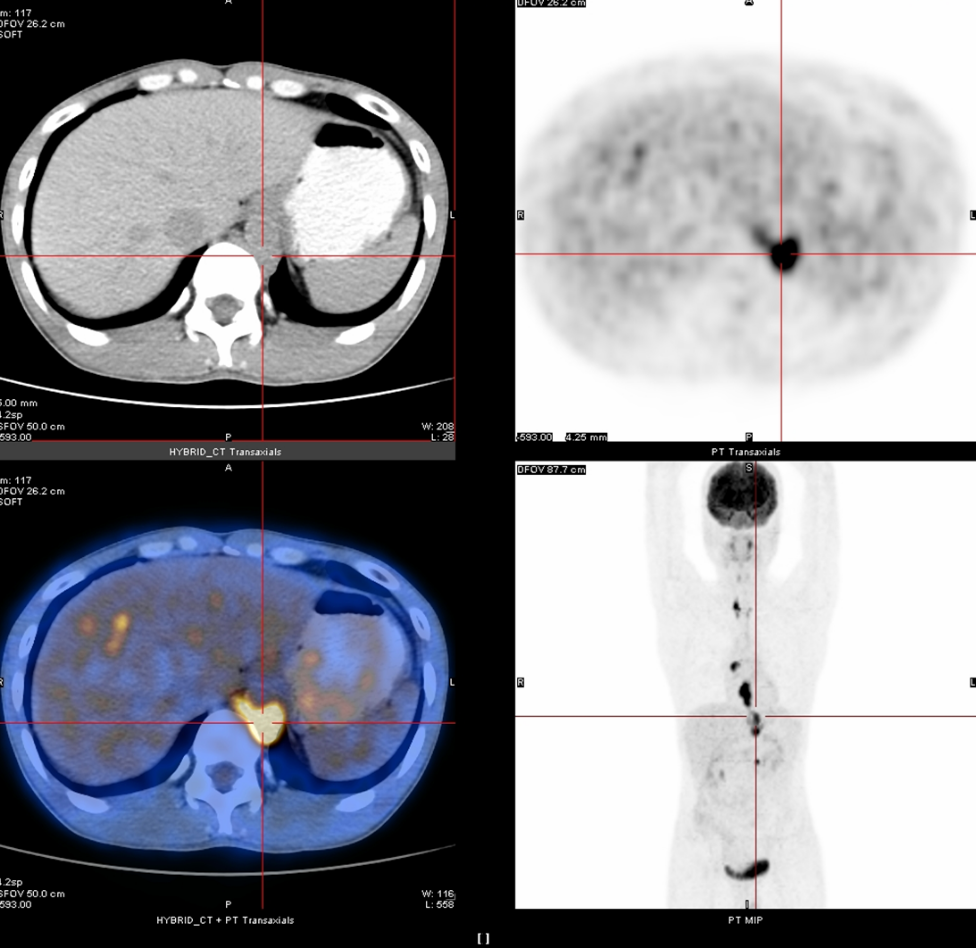

2020年3月13日

全身PET-CT示:1、食管胸中下段管壁不规则增厚,代谢增高,考虑食管癌。2、上纵隔胸廓入口区气管两旁、右下肺静脉后方、贲门区、肝胃间隙、降主动脉后方、膈肌脚后方、腹膜后腹主动脉左旁(左肾门下方平面)见多发高代谢肿大淋巴结,考虑淋巴结转移,建议随访复查。3、右肺上叶前段胸膜下小结节影,代谢未见增高,建议随访复查。4、右肺下叶外基底段条索影,考虑慢性炎性改变。5、双侧上颌窦轻度慢性炎症。6、双侧颈部多发小结节影,代谢未见增高,考虑淋巴结慢性炎性增生。7、肝左叶内侧段小钙化灶。